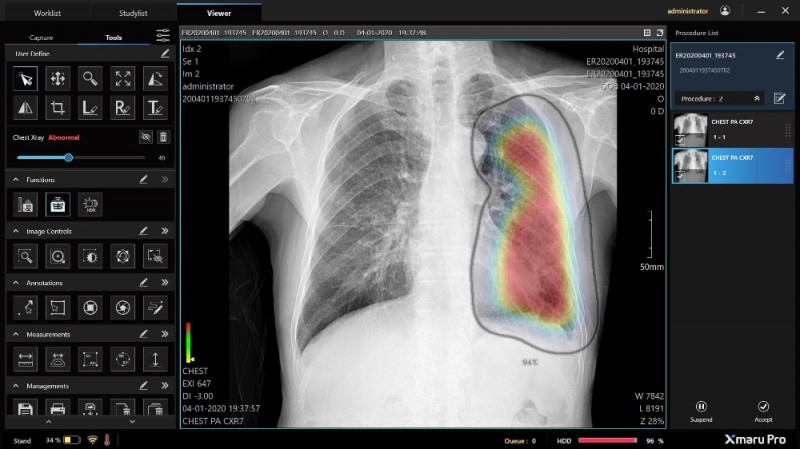

엑스마루 프로는 엑스선 발생장치와 디텍터를 거쳐 획득된 X-ray 영상을 처리해, PC/스마트기기 상에서 볼 수 있도록 의료 진단에 필요한 이미지와 정보로 전환하는 소프트웨어다. 영상처리 소프트웨어 가운데 AI 판독 지원 기능을 포함해 식약처 인증을 받은 것은 엑스마루 프로가 처음이다.

엑스마루 프로는 인터넷 연결 없이 흉부 엑스레이 영상에서 폐렴, 폐결핵, 폐질환 등의 소견을 AI로 자동 검출한다. 지금까지는 의료진이 AI 판독 지원 기능을 쓰려면 촬영된 영상 이미지를 내려 받아 인터넷으로 클라우드 서버와 연결하고, 전송하는 등의 절차를 거쳐야 했다. 이 과정에서 10분 이상의 시간이 소요됐다.

‘엑스마루 프로’는 AI 솔루션 기업 ‘주식회사 뷰노’의 ‘뷰노메드 체스트 엑스레이™’를 레이언스 디텍터 영상에 최적화했다. 흉부 엑스레이 영상에서 ▷경화(consolidation) ▷간질성 음영(interstitial opacity) ▷흉막삼출(pleural effusion) ▷결절(nodule) ▷기흉(pneumothorax) 등 5가지 소견을 신속하게 탐지할 수 있다.